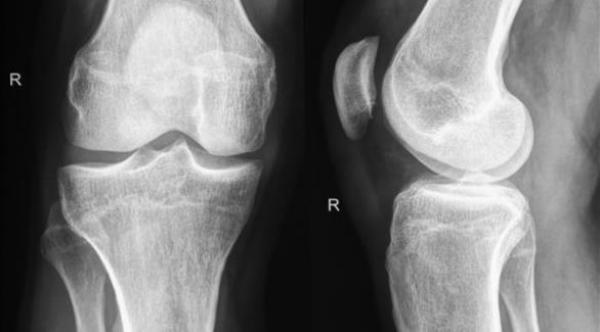

العلاج الهرموني يحسن صحة العظام بعد سن اليأس